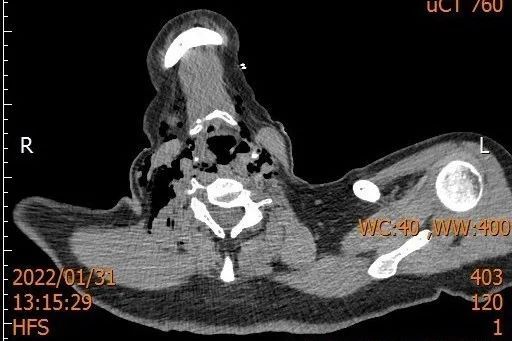

1月31日是中国的传统节日除夕,普陀区的孙女士为了晚上的年夜饭而忙碌着,可是她没有料想到一场意外悄然而至。为了打开一瓶自酿的米酒她想了各种办法,最后准备用嘴把瓶盖咬开,这时意外发生了,瓶子在她的嘴里炸开,巨大的气流把她的咽喉炸伤,顿时她感觉无法讲话和呼吸,鲜血从嘴里涌了出来。家人赶忙叫救护车把她送到医院。正在耳鼻咽喉头颈外科值班的张晓林医生和赵玉敏医生接到抢救室的电话后,第一时间来到病人床边为病人进行检查,查体后见患者咽喉活动性出血,软腭及双侧扁桃体上级可及裂伤,颈部可扪及捻发音,判断患者可能有皮下气肿,行喉部CT检查,报告提示:咽旁,颈部及纵隔,右上胸壁积气,舌骨体右侧骨折。患者的病情远比表面看到的复杂,需立即手术!